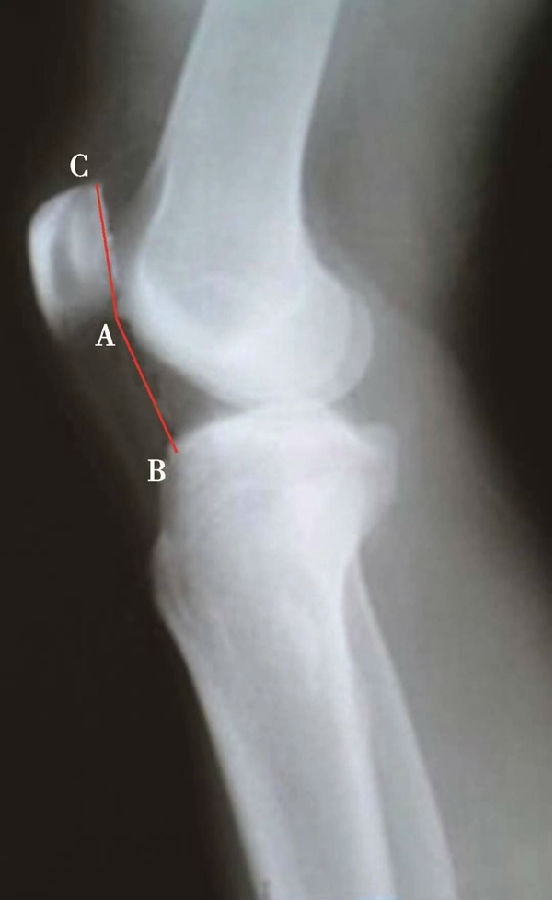

如图示:AB为髌骨关节面最低点到胫骨平台轮廓前上角最短的距离,AC是髌骨关节面的长度。Caton指数=AB/AC(图1)。

图2 Caton指数=AB/AC=1.10,为正常髌骨高度

临床工作中常常使用其来估计胫骨结节移位的效果。正常人的Caton指数=1,正常范围0.8~1.2(图2)。需要注意的是:术前规划胫骨结节需要移位的理论距离为AB-AC,这就是需要将胫骨结节向远端移位的最大距离。但在术中胫骨结节转移的距离往往要小于这个距离,避免因过度移位造成医源性的低位髌骨。